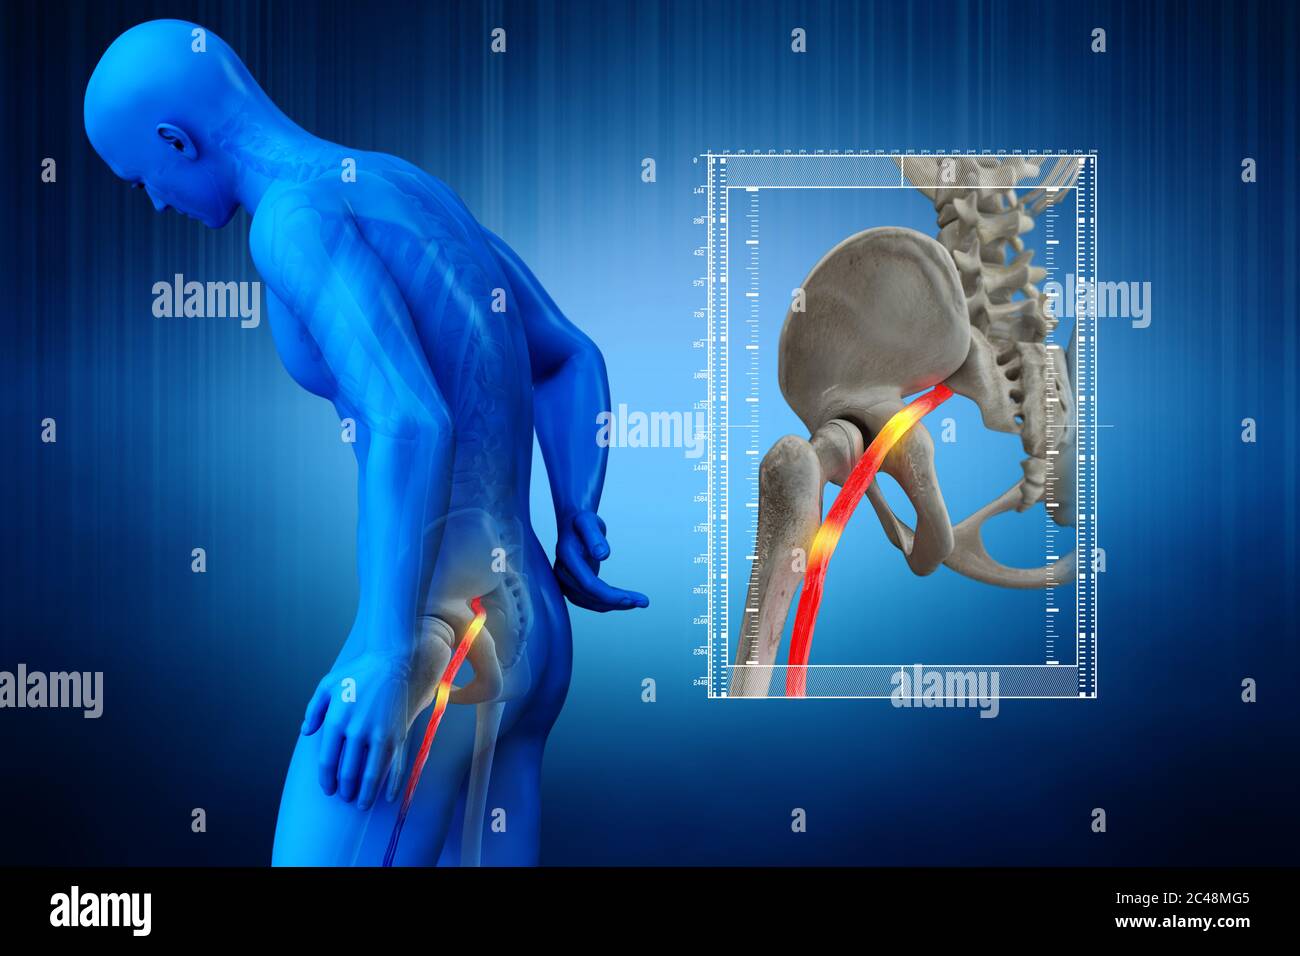

Nerf sciatique humain pincé, vision anatomique. illustration 3d. Banque D'Imageshttps://www.alamyimages.fr/image-license-details/?v=1https://www.alamyimages.fr/nerf-sciatique-humain-pince-vision-anatomique-illustration-3d-image364068055.html

Nerf sciatique humain pincé, vision anatomique. illustration 3d. Banque D'Imageshttps://www.alamyimages.fr/image-license-details/?v=1https://www.alamyimages.fr/nerf-sciatique-humain-pince-vision-anatomique-illustration-3d-image364068055.htmlRF2C48MEF–Nerf sciatique humain pincé, vision anatomique. illustration 3d.

Nerf sciatique humain pincé, vision anatomique. illustration 3d. Banque D'Imageshttps://www.alamyimages.fr/image-license-details/?v=1https://www.alamyimages.fr/nerf-sciatique-humain-pince-vision-anatomique-illustration-3d-image364067992.html

Nerf sciatique humain pincé, vision anatomique. illustration 3d. Banque D'Imageshttps://www.alamyimages.fr/image-license-details/?v=1https://www.alamyimages.fr/nerf-sciatique-humain-pince-vision-anatomique-illustration-3d-image364067992.htmlRF2C48MC8–Nerf sciatique humain pincé, vision anatomique. illustration 3d.

Nerf sciatique humain pincé, vision anatomique. illustration 3d. Banque D'Imageshttps://www.alamyimages.fr/image-license-details/?v=1https://www.alamyimages.fr/nerf-sciatique-humain-pince-vision-anatomique-illustration-3d-image364068117.html

Nerf sciatique humain pincé, vision anatomique. illustration 3d. Banque D'Imageshttps://www.alamyimages.fr/image-license-details/?v=1https://www.alamyimages.fr/nerf-sciatique-humain-pince-vision-anatomique-illustration-3d-image364068117.htmlRF2C48MGN–Nerf sciatique humain pincé, vision anatomique. illustration 3d.

Nerf sciatique humain pincé, vision anatomique. illustration 3d. Banque D'Imageshttps://www.alamyimages.fr/image-license-details/?v=1https://www.alamyimages.fr/nerf-sciatique-humain-pince-vision-anatomique-illustration-3d-image364068101.html

Nerf sciatique humain pincé, vision anatomique. illustration 3d. Banque D'Imageshttps://www.alamyimages.fr/image-license-details/?v=1https://www.alamyimages.fr/nerf-sciatique-humain-pince-vision-anatomique-illustration-3d-image364068101.htmlRF2C48MG5–Nerf sciatique humain pincé, vision anatomique. illustration 3d.

Nerf sciatique humain pincé, vision anatomique. illustration 3d. Banque D'Imageshttps://www.alamyimages.fr/image-license-details/?v=1https://www.alamyimages.fr/nerf-sciatique-humain-pince-vision-anatomique-illustration-3d-image364067990.html

Nerf sciatique humain pincé, vision anatomique. illustration 3d. Banque D'Imageshttps://www.alamyimages.fr/image-license-details/?v=1https://www.alamyimages.fr/nerf-sciatique-humain-pince-vision-anatomique-illustration-3d-image364067990.htmlRF2C48MC6–Nerf sciatique humain pincé, vision anatomique. illustration 3d.